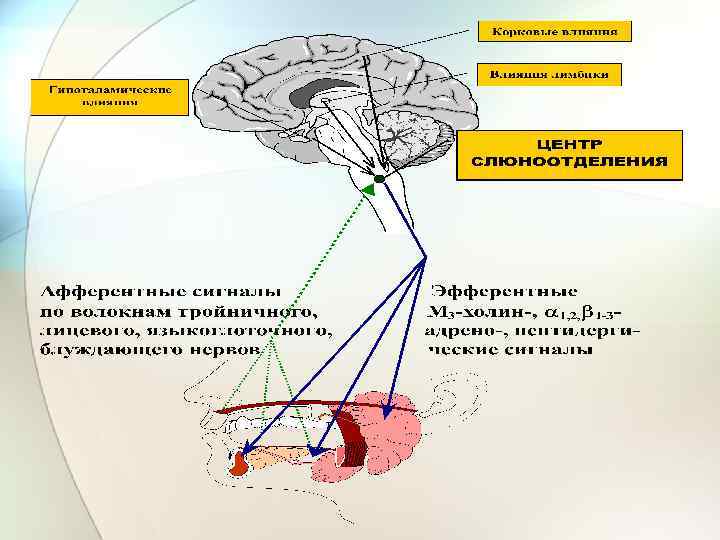

Все слюнные железы входят в состав аппаратов реакции ФУС формирования пищевого комка, адекватного для проглатывания. Аппаратами контроля являются рецепторы слизистой полости рта. Причем, если для жевания ведущими являются механорецепторы, для слюноотделения и слюнообразования ведущие вкусовые хеморецепторы. Афферентные возбуждения по тройничному нерву (V пара), лицевому (VII пара), языкоглоточному (IX пара), блуждающему (X пара) → достигают сенсорных ядер МО – n. tractus salitarius → переключаются на слюноотделительные ядра - n. solivatorius и в составе холинергических (парасимпатических) секреторных и адренергических (симпатических) трофических волокон через соответствующие эфферентные ганглии иннервируют соответствующие слюнные железы: n. salitarius Superior → подъязычная + поднижнечелюстная железы; ü n. solivatorius Inferior → околоушная железа.

Регуляция процессов слюноотделения и слюнообразования Холинергические нервные Адренергические нервные волокна. Возбуждение этих волокон вызывает выделение Аch и выделяется большое количество жидкой слюны, содержащей много солей и мало органических веществ. Такая слюна выделяется в ответ на попадание в полость рта некачественных, непригодных пищевых веществ или инородных тел => «отмывная слюна» . Преганглионарные волокна отходят от нейронов слюноотделительных ядер МО через вегетативные ганглии – постганглионарные волокна иннервируют слюнные железы. Парасимпатические влияния всегда сильнее симпатических. Их раздражение сопровождается высвобождением норадреналина и приводит к выделению небольшого количества слюны, богатой органическими веществами с малым содержанием солей. Преганглионарные волокна отходят от боковых рогов II - VI грудных сегментов спинного мозга и заканчиваются в верхнем шейном ганглии; отсюда постганглионарные н. в идут через plexus caroticus internus и достигают околоушной слюнной железы, а через plexus caroticus еxternus подъязычной и поднижнечелюстной железе.